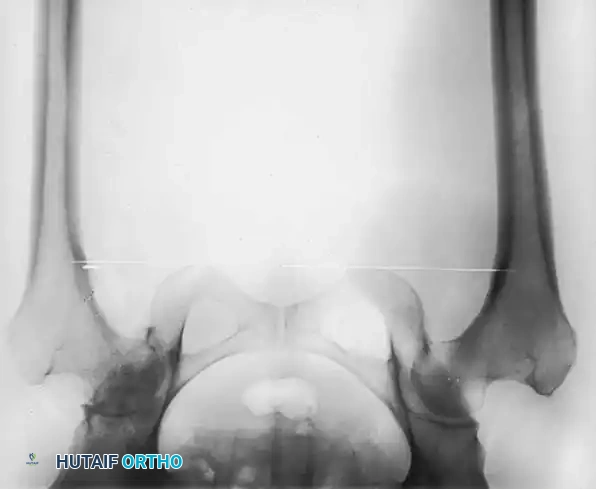

Standard preoperative radiographs must include an anteroposterior (AP) view of the pelvis centered over the pubic symphysis (with the hips internally rotated 15 degrees to profile the femoral neck) and a lateral view of the affected hip.

1. Determine Leg Length Discrepancy: A horizontal reference line is drawn across the bottom of the radiographic teardrops or the ischial tuberosities. The difference in the perpendicular distance from this line to a reproducible landmark on the proximal femur (usually the lesser trochanter) approximates the amount of limb shortening.

2. Acetabular Templating: The acetabular template is positioned at a 40- to 45-degree angle of inclination. It should correspond closely to the subchondral bone plate, ensuring adequate lateral coverage and medialization to the true floor (ilioischial line). The new center of rotation is marked.

3. Femoral Templating: The femoral template that most closely matches the proximal and distal size and contour of the femoral metaphysis and diaphysis is selected.

4. Neck Length and Offset: The neck length and offset are estimated to restore the abductor moment arm. The anticipated level of the femoral neck resection is marked relative to the lesser trochanter.

Fig. 7-40 Templating of radiographs for preoperative planning. A, Line drawn across the bottom of the pelvis to assess limb shortening. B, Acetabular template placed to mark the new center of rotation. C, Femoral template matching the metaphysis. D, Neck length and offset estimation.

Intraoperative and postoperative radiographs should confirm that the completed arthroplasty corresponds to the preoperative plan, with implants properly sized and leg length/offset correctly restored.